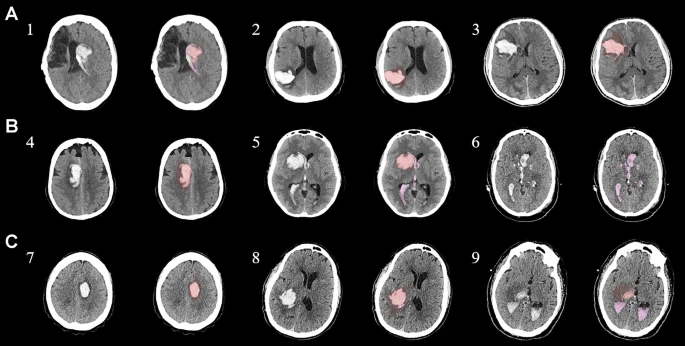

結合臨床特征的探索性成像容積模型分析

ABC/2模型1和模型2分割方法均通過線性回歸顯示出ICH和IVH體積的良好相關性(圖3a、b)。與模型2分割體積方法(例如每CT15-20分鐘)相比,模型1ABC/2衍生的半定量方法和改進的Graeb IVH方法所需的時間更短(例如2-5分鐘)。有趣的是,將NIHSS評分與IVH體積M2方法進行比較顯示出線性相關性(R2=0.7217),并且當IVH小于20mL或大于20mL時,NIHSS評分似乎存在聚集性(圖3c)。PHE 分析顯示MSC注射劑量與PHE體積之間存在輕微的負相關關系。